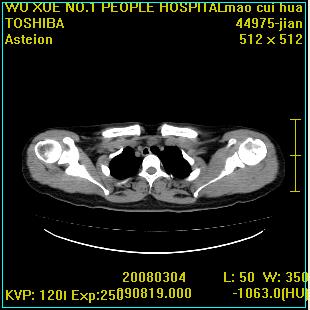

标题: CT12025:男,50岁,左肩活动受限半年。 [打印本页]

标题: CT12025:男,50岁,左肩活动受限半年。

肩关节骨质破坏呈小囊状,其周软组织轻度肿胀,余未见异常。

考虑:肩袖损伤。建议mri。

左侧肱骨头密度不均匀,高低混杂,周围软组织略肿胀,考虑结核性病变。

左侧肱骨头密度不均匀,高低混杂,髓腔密度稍高,周围软组织略肿胀,肌间隙模糊,考虑慢性骨髓炎可能。密切结合临床!